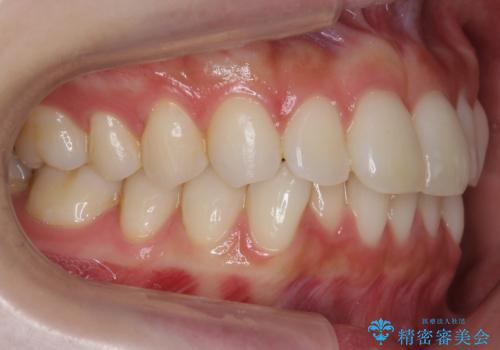

昔ワイヤー矯正をして後戻りした 軽度のがたつき モニター矯正

- 矯正治療後の後戻りを主訴に来院。

特に下の前歯のがたつきを気にされていました。

マウスピース矯正で再矯正を行いました。

再度の後戻りを防ぐため、下顎前歯の裏にはワイヤーを貼る保定を行っています。